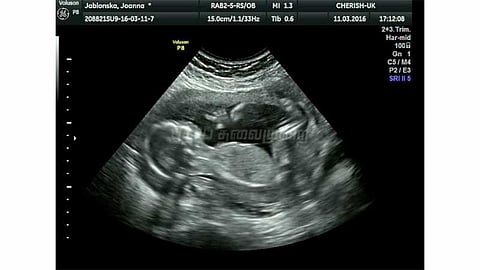

இணையம் மூலம் கருவின் பாலினம் கண்டறியும் வசதியை நீக்க புதிய அமைப்பு

கருவில் இருக்கும் குழந்தைகளின் பாலினத்தை கண்டறிவது தொடர்பான தகவல்களை இணையதளங்களில் இருந்து நீக்குவது தொடர்பாக அமைப்பு ஒன்றை மத்திய அரசு ஏற்படுத்தியுள்ளது.

கருவின் பாலினத்தை கண்டறிவது தொடர்பான விளம்பரங்கள், கருவிலிருக்கும் குழந்தையின் பாலினம் குறித்த தேடலை கூகுள், யாஹூ மற்றும் மைக்ரோசாப்ட் இணையதளங்களிலிருந்து நீக்குவது உள்ளிட்ட பணிகளை அந்த அமைப்பு செய்யும் என அரசின் சொலிசிட்டர் ஜெனரல் ரஞ்சித் குமார் நீதிமன்றத்தில் தெரிவித்தார். இந்தியாவில் ஆண் - பெண் விகிதாச்சாரம் வெகுவாக குறைந்து வருவதாக சாபு மேத்யூ ஜார்ஜ் என்ற மருத்துவர் தொடர்ந்த பொது நல மனுவில் இந்த உறுதிமொழியை மத்திய அரசு அளித்துள்ளது. இணையதளத்தில் பாலினத்தை கண்டறியும் வழிமுறைகளை பயன்படுத்தி பல தம்பதிகள் பெண் குழந்தைகளை கருவிலேயே கலைத்து வருவதாகவும் குற்றச்சாட்டு எழுந்துள்ளது குறிப்பிடத்தக்கது.